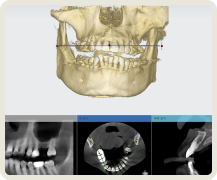

많은 치과의사들이 보철 중심으로 계획된 임플란트 시술의 중요성을 인정합니다.

그리고 이 과정에서 디지털 치과로의 전환이 필요함을 인정합니다.

이제는 임플란트 회사, 임플란트 브랜드 선택의 관점에서 벗어나서 임플란트 수술 진단부터 최종 치아 제작까지. 이 모든 과정에서 보철학적 목표를 디지털 방식으로 어떻게 완성해 내는지가 선택의 관점이 되어야 합니다.

이로운 치과는 간단하고 정확하며 안전한 치료를 위한 디지털 진료 방식을 지향합니다.

이로운 치과는 디지털 진료를 통해 정확한 임플란트 식립 위치를 파악하여

아날로그 치료에서 발생할 수 있는 문제를 예방합니다.

개인 맟춤 디지털 수술 가이드

덴티움 임플란트

환자 맞춤형 지대주

CAD/CAM 지르코니아 크라운

이 모든 술식, 장비, 소프트웨어 노하우가 집약된

이로운치과의 디지털 임플란트